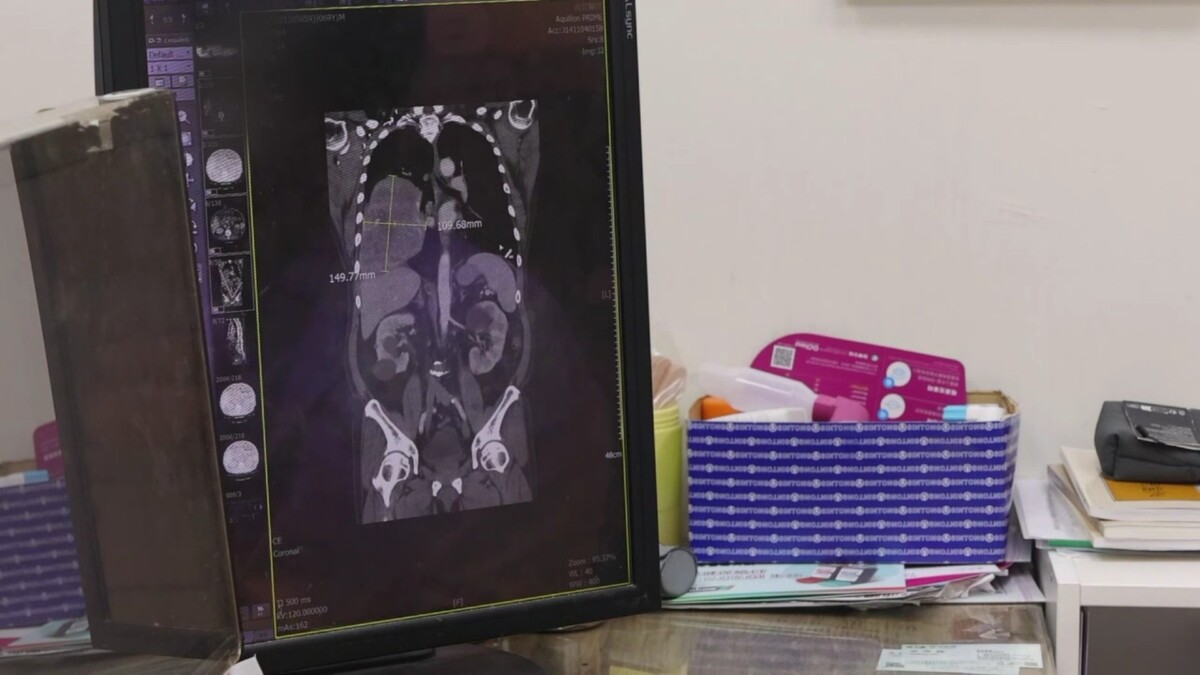

▲70歲男反覆低血糖昏迷,檢查驚見右肺15公分腫瘤,確診罕見腫瘤相關低血糖症,術後恢復良好。(員榮醫院提供)

▲70歲男反覆低血糖昏迷,檢查驚見右肺15公分腫瘤,確診罕見腫瘤相關低血糖症,術後恢復良好。(員榮醫院提供)

住院期間,患者仍頻繁發生低血糖,血糖多次低於30 mg/dL,需持續注射高濃度葡萄糖維持生命穩定。進一步胸部影像檢查發現,右肺存在一顆約15×11公分巨大腫瘤,並伴隨肋膜積液與淋巴結腫大。

院方隨即會診胸腔專科,由涂川洲參與評估,醫療團隊高度懷疑為罕見「腫瘤相關低血糖」,可能與腫瘤分泌類胰島素生長因子(IGF-2)有關,屬於非胰島素瘤性低血糖症(NICTH)。

後續跨科合作,由在員榮駐診的胸腔外科醫師 李佳穎操刀,採胸腔鏡輔助迷你開胸手術完整切除腫瘤。術後病理證實為罕見「肺部單發性纖維瘤」,約5%患者可能合併低血糖症狀。